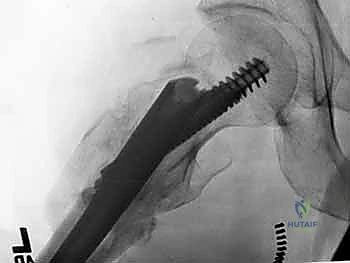

1. المسمار النخاعي الرئيسي (Intramedullary Nail): مسمار طويل يمتد داخل القناة النخاعية لعظمة الفخذ.

2. المسمار الرأسي/العنقي (Cephalic/Lag Screw): مسمار سميك وقوي يمر من خلال الجزء العلوي للمسمار النخاعي، ويدخل في عنق ورأس عظمة الفخذ لتثبيت الكسر الرئيسي.

3. مسامير الغلق السفلية (Distal Locking Screws): مسامير صغيرة تُثبت أسفل المسمار النخاعي لمنعه من الدوران أو الانزلاق داخل العظم.

هذا التصميم العبقري يجعله أقوى نظام تثبيت متوفر حالياً، حيث يمر محور تحمل الوزن عبر المسمار الموجود داخل العظم، مما يجعله مقاوماً للكسر والانحناء، ويسمح للمريض بالاعتماد على ساقه في وقت قياسي.

5. تثبيت عنق ورأس الفخذ (المسمار الرأسي)

من خلال ذراع توجيه متصلة بالمسمار الرئيسي، يتم إحداث ثقب في عنق ورأس عظمة الفخذ. يتم إدخال المسمار الرأسي (Cephalic Screw) السميك ليمسك برأس الفخذ بقوة ويسحبه نحو المسمار الرئيسي، مما يضغط الكسر (Compression) ويحفز التئام العظام بسرعة.